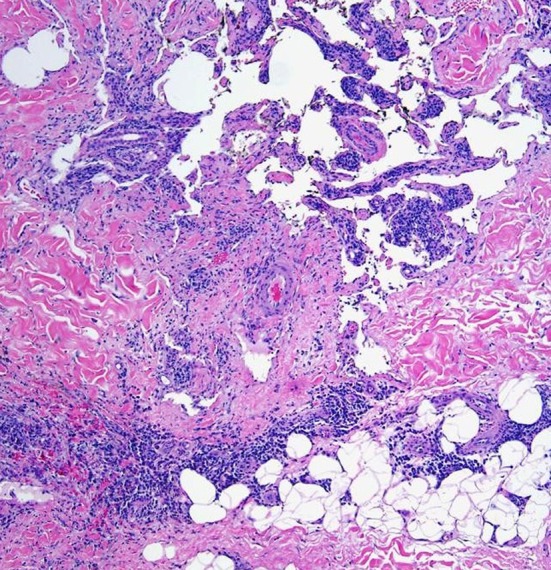

Fig. 6.

Multiple lymphatic channels containing few blood vessels, adipose tissue, and fibrous tissue (H and E, ×40)

A 6 year old male patient was referred to the department of oral and maxillofacial surgery with a chief complaint of large swelling on the right side of the jaw for past 2 years. Examination of the patient revealed soft, diffuse, mobile large swelling over the submandibular region (Fig. 1a, b). Swelling was small in size initially which gradually increased in size. The swelling was 12×8 cm in size non-tender, mobile, non-pulsatile, cystic in consistency, non-compressible and fluctulant. Transillumination test was positive and aspiration of the lesion resulted in brownish fluid. Clinical diagnosis of cystic hygroma was made. CT scan showed the extent of the tumor and showed large cystic lesion with definite boundaries (Fig. 2). The patient was then admitted for surgical removal of the lesion under general anesthesia. Through a submandibular incision, the lesion was completely excised (Figs. 3, 4). The facial nerve branches were identified and preserved. Careful dissection of the lesion anteriorly up to the midline, superiorly up to the lower border of the mandible, and posteriorly up to the tail of the parotid was carried out. The masses were separated from their attachment to sternocleidomastoid muscle. Hemostasis was achieved using cautery and ligation. Wound closure was done, by suturing the subcutaneous tissue followed by fascia and skin. The patient was hospitalized for 3 days and was discharged in a satisfactory condition (Fig. 5). There was no facial nerve deficit and patient is under regular follow up. The surgical specimen measured 7 × 5 cm, appeared irregular in shape but was well circumscribed. Cut surface revealed multiple cyst like spaces separated by thin fibrous septae and filled with gelatinous material and few cystic spaces filled with blood (Fig. 4). Histopathology revealed varying proportions of large and small lymphatic channels containing lymph, few blood vessels, adipose tissue, fibrous tissue, and lymphoid tissue. Areas of haemorrhage were also seen (Fig. 6). Based on the microscopic observations in correlation with clinical features, a final diagnosis of cystic hygroma was made.